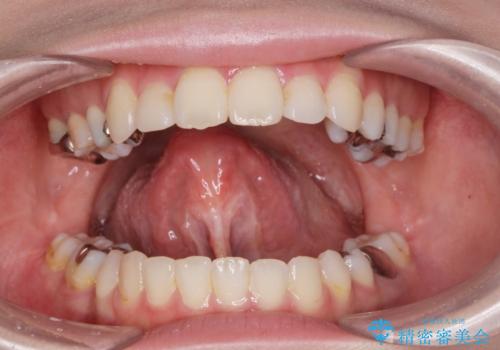

[ 舌小帯の形成術 ] 「ら行」や「た行」が発音しづらいのを改善したい!

担当医 大元洋佑

![[ 舌小帯の形成術 ] 「ら行」や「た行」が発音しづらいのを改善したい!の症例 治療前](https://seimitsushinbi.jp/wp/wp-content/uploads/2023/12/7d9ac5f7c2f3679a481af9859a64f532-500x350.jpg?v=1701830486)

![[ 舌小帯の形成術 ] 「ら行」や「た行」が発音しづらいのを改善したい!の症例 治療後](https://seimitsushinbi.jp/wp/wp-content/uploads/2023/12/999705bbf9ee513b86dbb3839372e65b-500x350.jpg?v=1701830502)